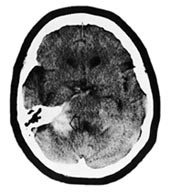

Pasient 1. 51 år gammel kvinne som 25 år før det aktuelle hadde gjennomgått en subaraknoidalblødning. Cerebral angiografi hadde vist en sentralt beliggende arteriovenøs malformasjon i høyre frontallapp. Denne ble vurdert som inoperabel grunnet sin størrelse og beliggenhet. Fire måneder før den aktuelle episode hadde hun konsultert nevrolog for svimmelhet. CT caput ved den anledning viste en stor malformasjon i høyre frontalregion, med rikelig opptak av kontrast (fig 1). Malformasjonen bredte seg over midtlinjen.

Figur 1   CT caput av pasient 1 fire måneder før hun igjen ble innlagt med subaraknoidalblødning. Bildet viser en stor arteriovenøs malformasjon beliggende overveiende i høyre frontallapp med rikelig opptak av kontrast